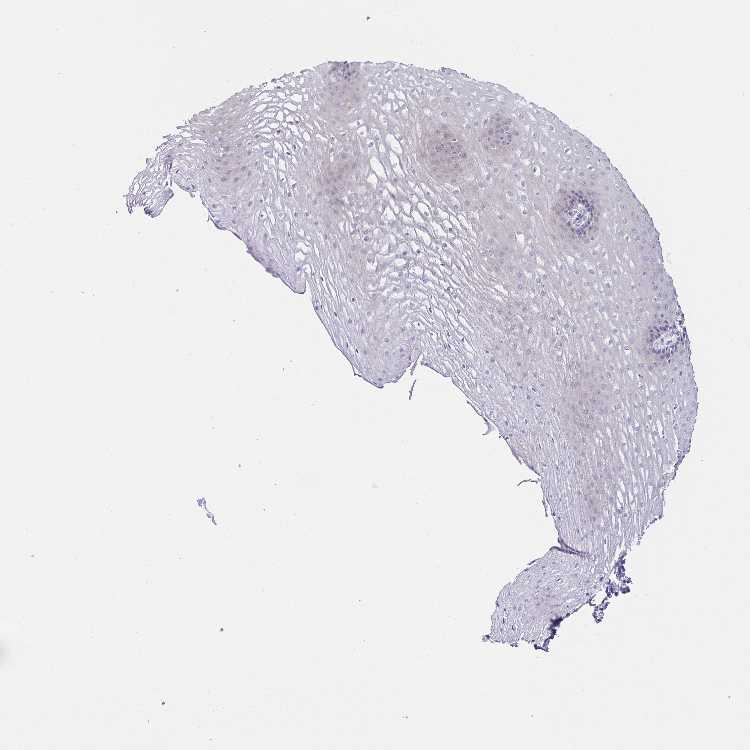

TISSUE PRIMARY DATA ESOPHAGUS Show tissue menu

ESOPHAGUS - Antibody stainingi

Antibody staining in the annotated cell types in the current human tissue is reported as not detected, low, medium, or high, based on conventional immunohistochemistry profiling in selected tissues. This score is based on the combination of the staining intensity and fraction of stained cells.

Each image is clickable and will lead to virtual microscopy that enables deeper exploration of all samples and also displays staining intensity scores, fraction scores and subcellular localization as well as patient and tissue information for each sample.

Antibody HPA039149Antibody HPA061446Antibody CAB034450

Squamous epithelial cells LowNot detectedNot detected